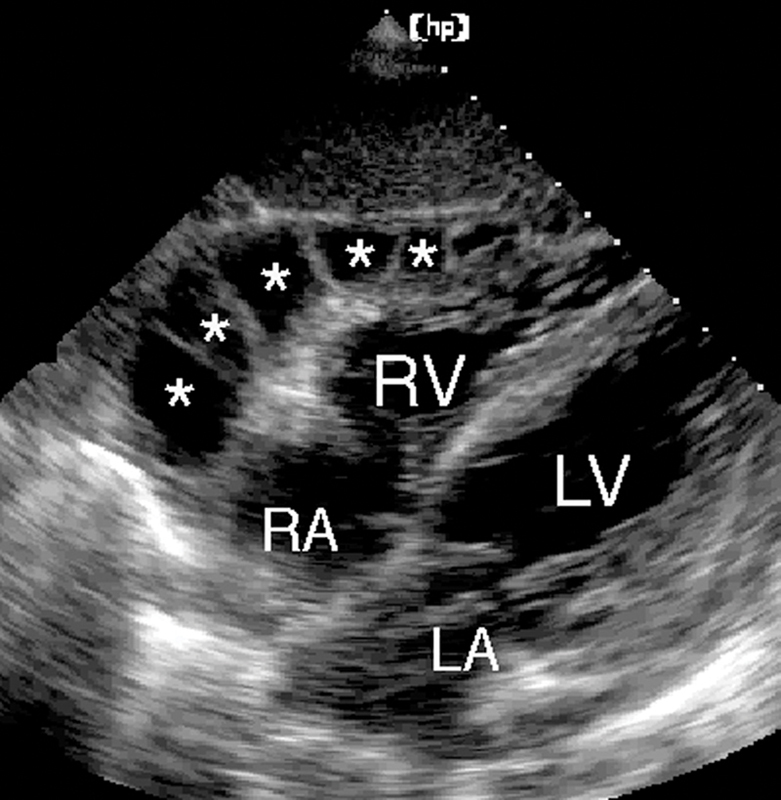

فحوصات تشخيصية لبعض امراض القلب والشرايين التاجية